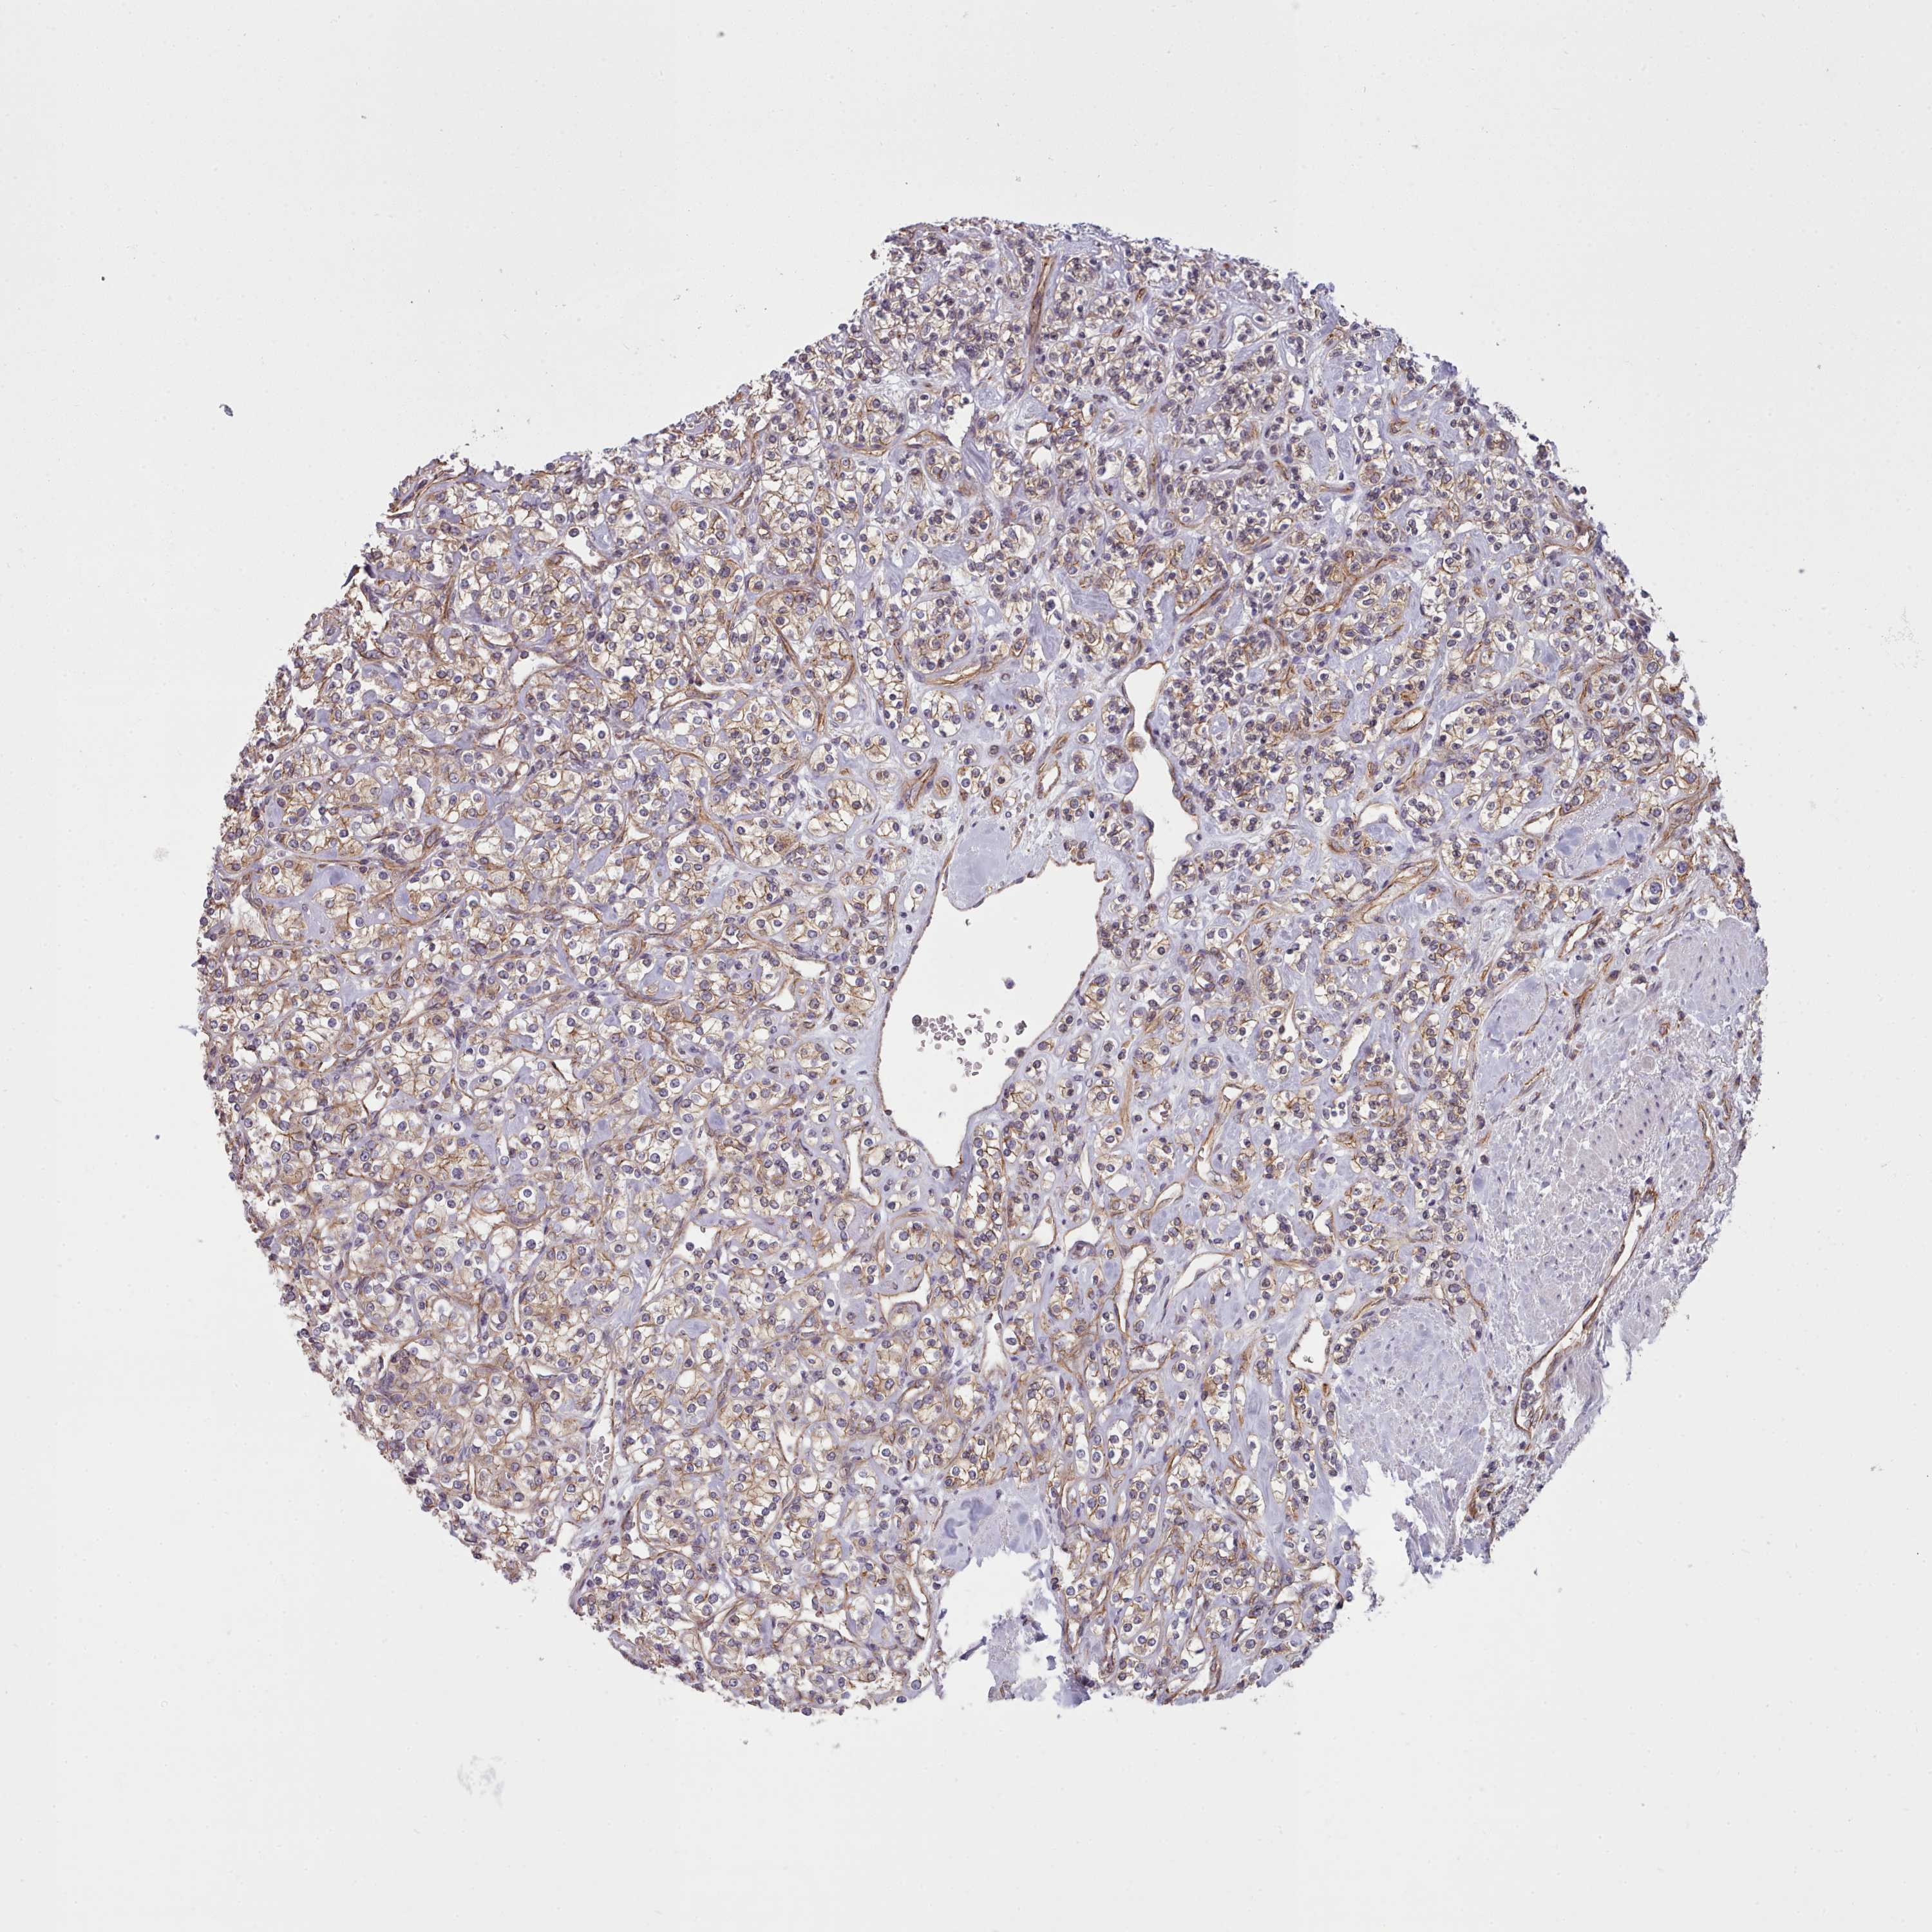

KIDNEY RENAL CLEAR CELL CARCINOMA (VALIDATION) - Interactive survival scatter ploti

The Survival Scatter plot shows the clinical status (i.e. dead or alive) for all individuals in the patient cohort, based on the same data that underlies the corresponding Kaplan-Meier plots. Patients that are alive at last time for follow-up are shown in blue and patients who have died during the study are shown in red.

The x-axis shows the expression levels (FPKM) of the investigated gene in the tumor tissue at the time of diagnosis. The y-axis shows the follow-up time after diagnosis (years). Both axes are complimented with kernel density curves demonstrating the data density over the axes. The top density plot shows the expression levels (FPKM) distribution among dead (red) and alive patients (blue). The right density plot shows the data density of the survived years of dead patients with high and low expression levels respectively, stratified using the cutoff indicated by the vertical dashed line through the Survival Scatter plot. This cutoff is automatically defined based on the FPKM cutoff that minimizes the p-score. The cutoff can be changed by dragging the vertical line or by entering a cutoff value in the square labeled "Current cut-off".

Under the Survival Scatter plot the p-score landscape (black curve; left axis) is shown together with dead median separation (red curve; right axis). Dead median separation is the difference in median mRNA expression between patients who have died with high and low expression, respectively. It is calculated as follows: median FPKM expression of dead patients with high expression - median FPKM expression of dead patients with low expression. This is intended to aid the user in visually exploring custom cutoffs and the associated p-scores and dead median separation.

Individual patient data is displayed and can be filtered by clicking on one or more of the category buttons on the top of the page. Categories describing expression level and patient information include: high, low, alive, dead, female, male and tumor stages. The scale of the x-axis can be toggled between linear and log-scale by clicking on the "x log" button. Mouse-over function shows TCGA ID, patient information and mRNA expression (FPKM) for each patient.

& Survival analysisi

Kaplan-Meier plots summarize results from analysis of correlation between mRNA expression level and patient survival. Patients were divided based on level of expression into one of the two groups "low" (under cut off) or "high" (over cut off). X-axis shows time for survival (years) and y-axis shows the probability of survival, where 1.0 corresponds to 100 percent.

MRPL46 is validated prognostic, high expression is favorable in Kidney Renal Clear Cell Carcinoma (validation)

Best expression cut offi

Based on the FPKM value of each gene, patients were classified into two groups and association between prognosis (survival) and gene expression (FPKM) was examined. The best expression cut-off refers the FPKM value that yields maximal difference with regard to survival between the two groups at the lowest log-rank P-value. Best expression cut-off was selected based on survival analysis .

When clicking on this number, the vertical dashed line indicating cut-off, the interactive survival plot, and the Kaplan-Meier curve will be adjusted to show results based on the best expression cut-off.

: 29.85

Average pTPM 30.3

Number of samples 100